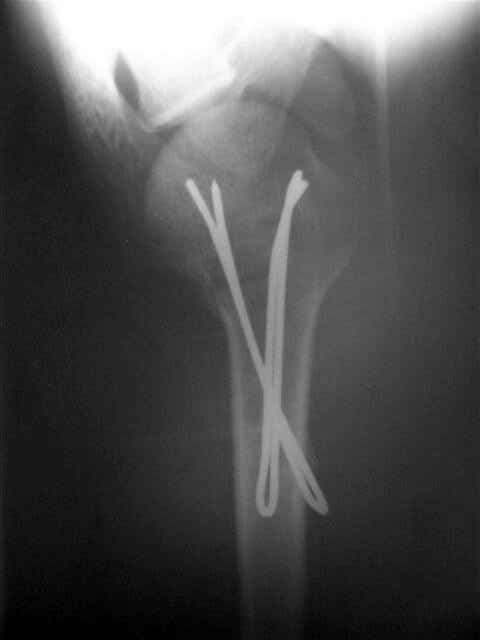

Сегодня взял больного повторно в операционную, не скажу, что повторная репозиция через неделю после первой попытки, была простая.

После удаления спиц попытался манипулировать отломками, но безуспешно, поэтому пришлось пользоваться периостальным элеватором, чтобы устранить смещение отломков и перепровести спицы. Проверил и перепроверил стабильность фиксации под ЭОПом, завтра Рг- будет готов, вот и поглядим....

Посылаю послеоперационные Рг граммы.

Всего Доброго,

Евгений И Чекашкин

Спасибо за поздравления:-))

Я и сам доволен результатом. В предпоследнем письме я кратко описал ход операции - закрыто репонировать не удалось( 2 недели с момента травмы и 1 неделя после неудачной репозиции) после удаления пучков спиц, пришлось сделать - 2см разрез на уровне перелома и с помощью периостального элеватора (золотое правило механики) *одеть* головку на дистальный отломок.

Спицы проводил через старые отверстия, вращая пучок импактором- направителем при его введении в головку.